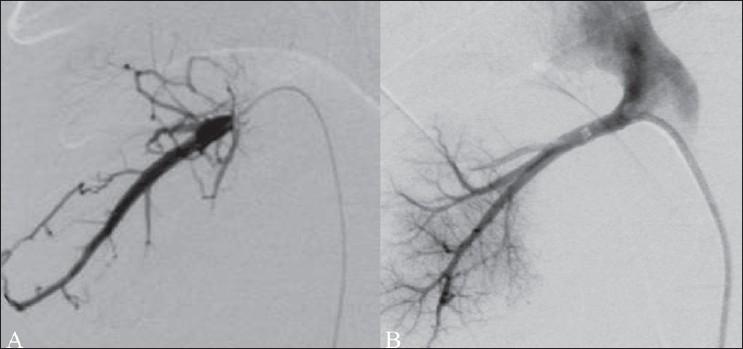

From being a mere (though important) diagnostic tool, radiology has evolved to become an integral part of therapy in portal hypertension today. Various procedures are currently available, the choice depending on the etiology and location of disease, the pathoanatomy, and the symptomatology. The main aim of any procedure is to reduce the portal pressure by either direct or indirect methods. This can be achieved with transjugular intrahepatic portosystemic shunt (TIPS), recanalization of the hepatic vein outflow, recanalization of the portal vein and its tributaries, recanalization of dysfunctional portosystemic shunts, partial splenic embolization, and embolization of arterioportal shunts. When any of these procedures cannot be performed due to anatomical or physiological reasons, the symptoms can often be controlled effectively with embolization of varices or balloon-occluded retrograde transvenous obliteration of varices (BRTO). This article briefly describes the procedures, their results, and their current status in the treatment of portal hypertension.

从仅仅作为一种(尽管很重要的)诊断工具,放射学如今已发展成为门静脉高压治疗中不可或缺的一部分。目前有多种治疗方法可供选择,具体选择取决于疾病的病因和位置、病理解剖结构以及症状表现。任何治疗方法的主要目的都是通过直接或间接的方式降低门静脉压力。这可以通过经颈静脉肝内门体分流术(TIPS)、肝静脉流出道再通、门静脉及其分支再通、功能失调的门体分流再通、部分脾栓塞以及动脉门静脉分流栓塞来实现。当由于解剖学或生理学原因无法进行上述任何一种治疗方法时,通常可以通过曲张静脉栓塞或球囊闭塞逆行静脉曲张静脉闭塞术(BRTO)有效地控制症状。本文简要介绍了这些治疗方法、它们的治疗效果以及在门静脉高压治疗中的现状。